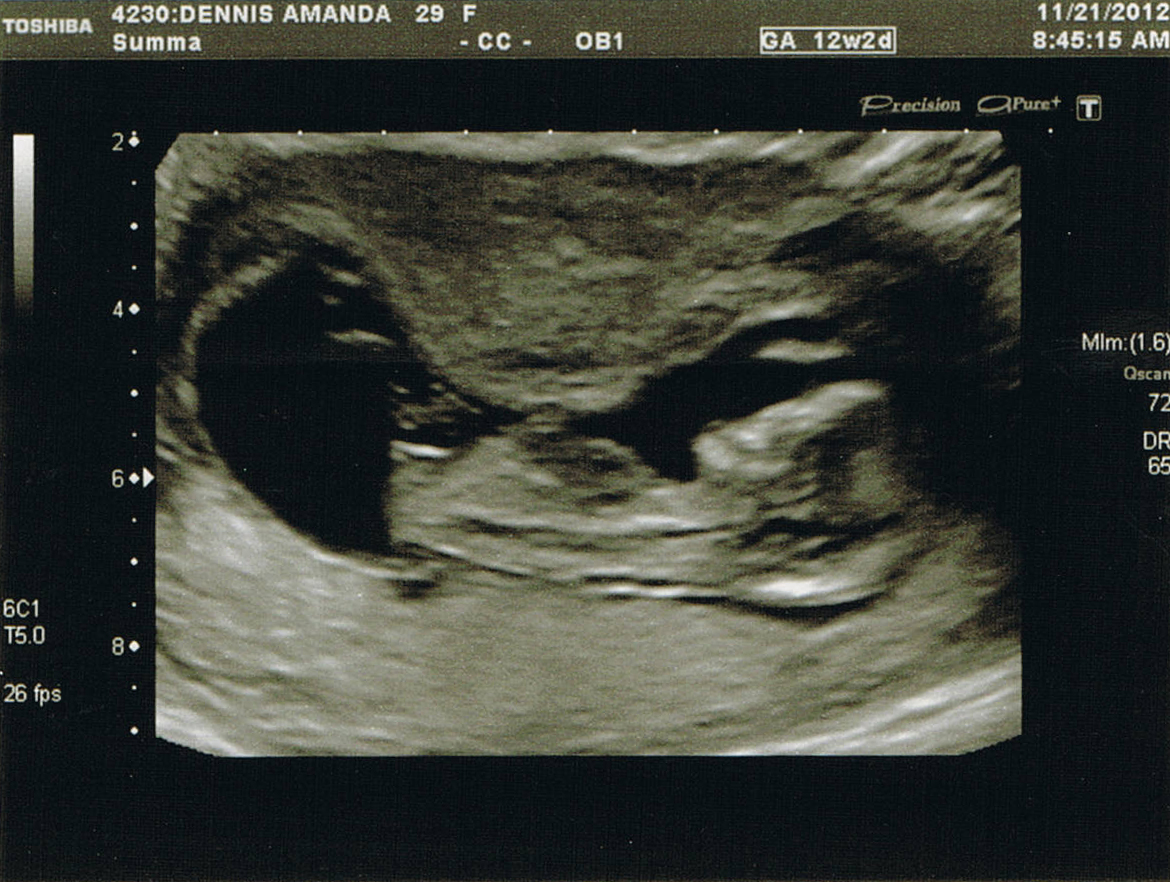

Thank you! Just in case you didn't see my first post, here are the good "nub shots" lol. Thanks again!Attachment 7074Attachment 7075

Second pic looks like my confirmed girl nub. Good luck!